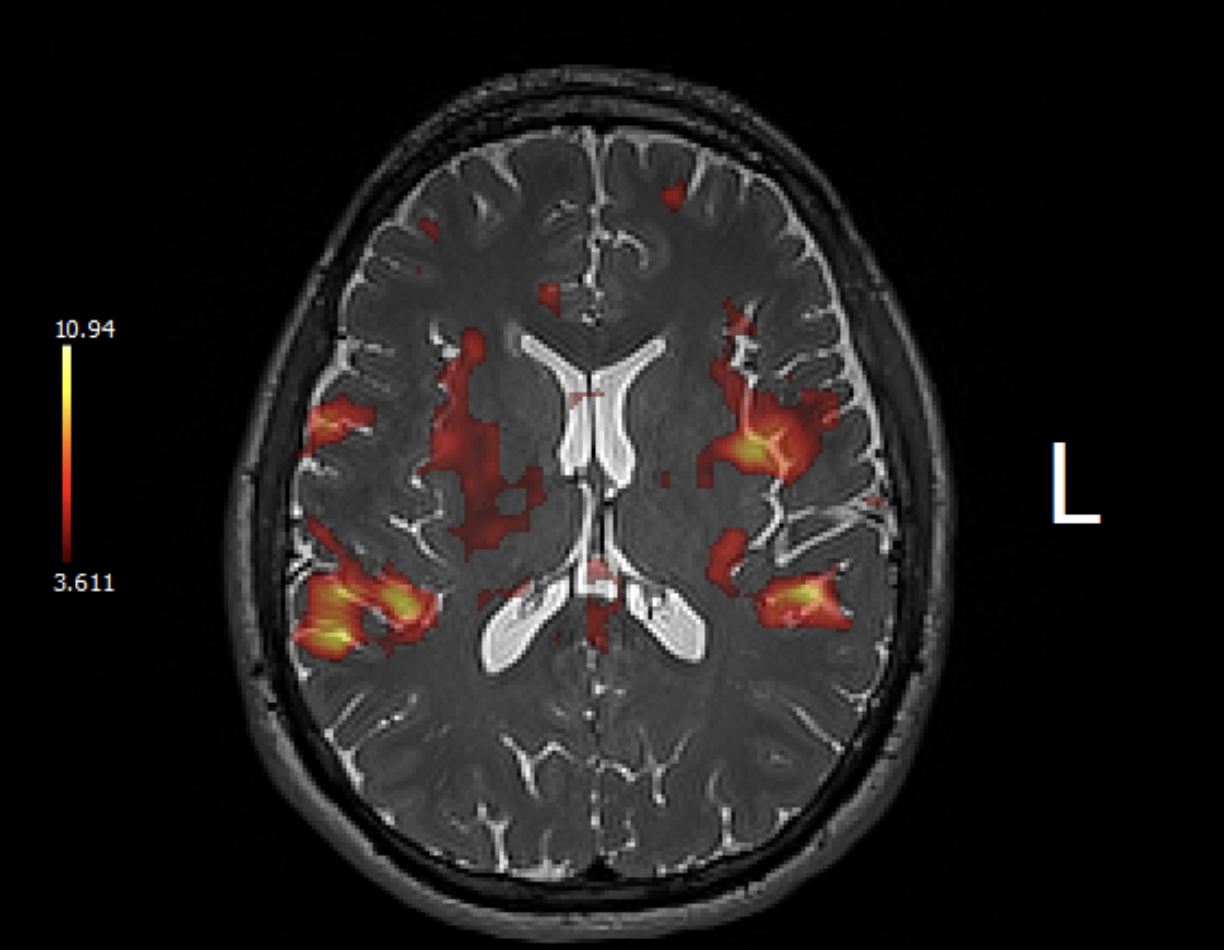

Interesting fMRI pictures (interesting note is that I was able to obtain these myself using my patient portal and scrolling through the MRI test!):

Image of me tapping my right fingers together: